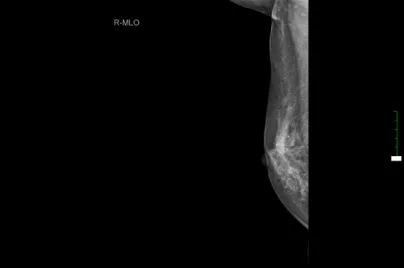

现病史:患者3年余前无意中发现右乳头后方有一肿块,约“枣样”大小,皮肤略红肿,无糜烂,乳头无溢血溢液,就诊于当地医院,建议定期复查处理。3年余来肿块逐渐增大,现约如“核桃样”大小,皮肤“橘皮样”变伴红肿,无发热,遂就诊于淮阳县人民医院,行乳腺彩超示:右乳实性占位(36x15mm),行乳腺钼钯示:右侧乳腺高密度块状影(2.9cmx4.0cm),建议进一步检查。今患者为求进一步诊治来我院就诊,门诊诊断为:“右乳肿块:乳腺癌?”,建议进一步治疗,遂收入院。

双乳彩超:右乳低回声肿块,BI-RADS 4C类,右侧腋窝淋巴结增大。

胸部CT: 1、右侧乳腺区占位并右侧腋窝、右侧胸大肌内侧多发淋巴结肿大。2、纵隔淋巴结可见,个别肿大。3、双肺临近肺底区炎性机化性改变。4、右侧肾上腺局部占位。